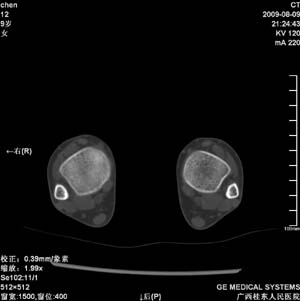

标题: PED2867:右侧内踝肿胀,骨质改变,请各位老师会诊 [打印本页]

标题: PED2867:右侧内踝肿胀,骨质改变,请各位老师会诊

九岁小朋友,近期左侧内踝疼痛,局部肿胀,平时无特殊,近期经常溜干冰

对不起,是右侧内踝肿胀

双踝关节骨质及发育未见异常。